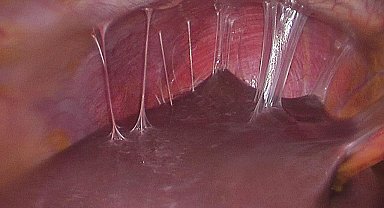

Ses teli bozukluğuna kişinin kendi kanından şifa